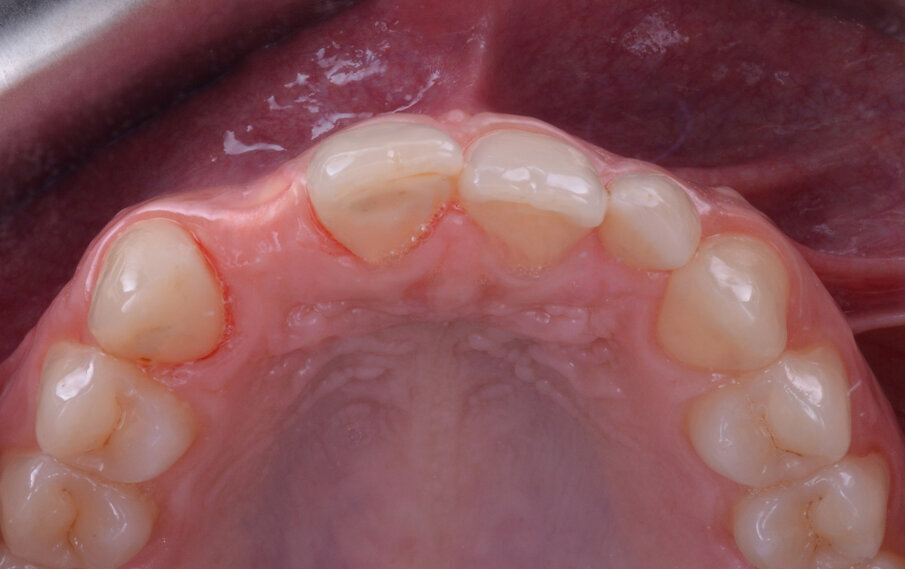

Gli esami radiografici completano l’approccio diagnostico iniziale e lo studio delle radiografie endorali del gruppo frontale, di un’ortopantomografia delle arcate dentarie e di una CBCT permettono di evidenziare un corretto allineamento radicolare degli elementi dentari contigui all’edentulia da trattare e una moderata atrofia orizzontale della cresta alveolare edentula (Fig. 1). Trattandosi di una riabilitazione del settore frontale è opportuno realizzare una dettagliata analisi estetica supportata da un esame fotografico corredato di fotografie extraorali (del volto e del sorriso), fotografie intraorali e da una ceratura diagnostica. L’attenzione iniziale è rivolta principalmente all’analisi dei tessuti molli e degli elementi dentari; in particolare, nel caso descritto, la paziente non presenta fattori estetici sfavorevoli dal momento che si riscontra la presenza di una linea del sorriso media, elementi dentari in area estetica sani e non discromici, fenotipo gengivale spesso, simmetria della festonatura gengivale e buona rappresentazione delle papille interdentali. Osservando in visione frontale la situazione clinica iniziale si evidenzia una lieve recidiva ortodontica dell’elemento 1.1 che si presenta leggermente mesializzato e vestibolarizzato rispetto alla sua posizione ideale (Fig. 2).

Le visioni laterale e occlusale permettono di evidenziare la presenza di un minus vestibolare in regione 1.2 da intendere come conferma clinica della moderata atrofia orizzontale del processo alveolare già in precedenza intercettata durante lo studio della CBCT (Figg. 3, 4). La richiesta della paziente è quella di giungere ad una riabilitazione protesica fissa che ponga fine all’attuale condizione di disagio vissuta nel condurre una vita di relazione caratterizzata da ripetuti distacchi del manufatto protesico provvisorio e che la soddisfi dal punto di vista estetico. Un colloquio preliminare con la paziente nel quale sono state contemplate differenti alternative terapeutiche ci permette di identificare come soluzione terapeutica una riabilitazione implanto-protesica in sede 1.2 ed il contestuale trattamento dell’atrofia ossea orizzontale con un apporto osseo mediante utilizzo di tecnica GBR; lo scopo di questo trattamento rigenerativo è di garantire la presenza di spessori ossei perimplantari adeguati ed il corretto ripristino dell’architettura convessa vestibolare per ottenere un soddisfacente mimetismo radicolare.

Fig. 4 - Situazione clinica iniziale (visione occlusale).